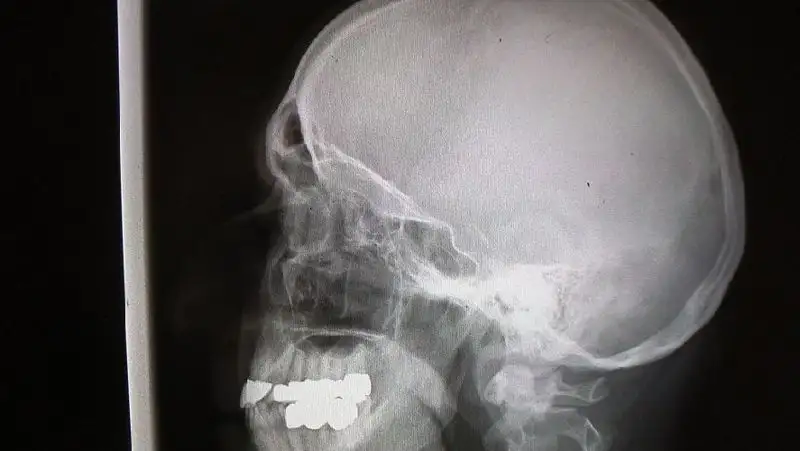

Течение тяжелой черепно-мозговой травмы в ряде случаев сопровождается оперативной трепанацией черепа по жизненным показаниям. После завершения острого периода травмы пациенты в плановом порядке консультируются у нейрохирурга. Это необходимо для решения вопроса по срокам и видам пластики дефектов черепа, показаниям и имеющимся противопоказаниям.

Краниопластика – нейрохирургическая операция с целью восстановления целостности черепа. Имеются разработанные требования к протезам: биологическая совместимость, прочность, пластичность, устойчивость к внешней температуре, отсутствие канцерогенности. Цель операции – герметизация полости черепа для защиты от внешних воздействий и нормализации внутричерепного кровообращения, устранение косметического дефекта. Заведующий отделением №2 в ГКБ №7 Алматы нейрохирург Ильдар Курмаев

Применяются методики ручного и 3D-стереолитографического компьютерного моделирования протезов из акриловых цементов, титановых сеток и пластин.